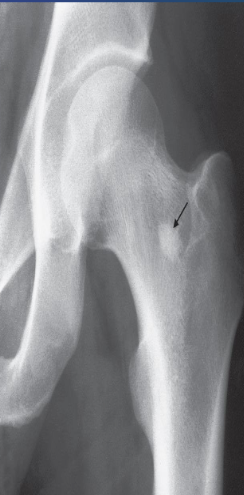

Impacted femoral neck

fracture (arrows) causing only a

sclerotic line and disruption of

the trabecular architecture.

Describe the lesion well-defined area of compact bone in the neck of the femur (arrow

Diagnosis This common finding is without significance.